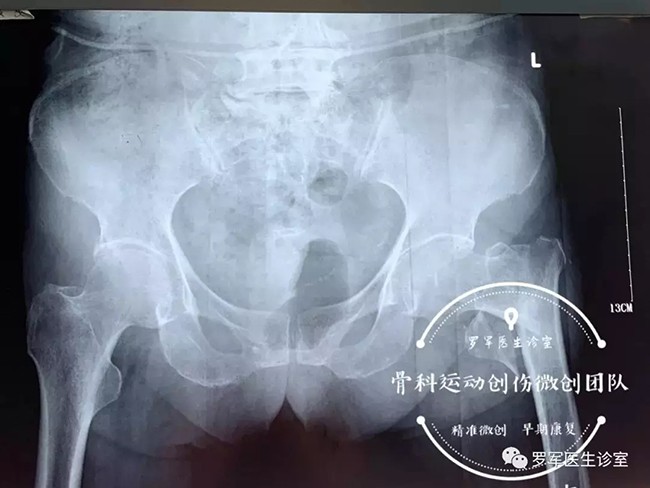

今年86歲高齡的丁奶奶就是其中的一位患者,前不久,丁奶奶走路時不幸摔倒,造成左側(cè)股骨粗隆間粉碎性骨折,被送到廣安醫(yī)院關(guān)節(jié)科救治。

經(jīng)過入院檢查發(fā)現(xiàn)丁奶奶合并有高血壓,糖尿病,動脈粥樣硬化、低蛋白血癥及嚴(yán)重的骨質(zhì)疏松,“無論采取保守治療還是手術(shù)治療,風(fēng)險(xiǎn)都很大。但對于高齡老人的骨折,放棄手術(shù)就等于放棄生的希望。”羅軍主任介紹,髖部骨折對高齡、身患各種慢性病的老年人來說無疑是大難題,而且由于骨折后老人臥床至少需要三個月以上,由此引發(fā)的并發(fā)癥,如褥瘡,肺炎、血栓、泌尿系感染等都很容易導(dǎo)致老人死亡。因此,髖部的骨折被稱為老年人“人生的最后一次骨折”。

5月7日,羅軍主任帶領(lǐng)手術(shù)團(tuán)隊(duì)按照術(shù)前的討論方案,在C臂機(jī)透視下,采用三個微創(chuàng)手術(shù)通道,施行精準(zhǔn)閉合復(fù)位、定位、固定,僅用了大約30分鐘,便成功完成微創(chuàng)內(nèi)固定手術(shù)。手術(shù)進(jìn)行順利,第二天老人就可以在床邊坐起了。老奶奶非常開心,叫家人一定要送面錦旗給醫(yī)生。